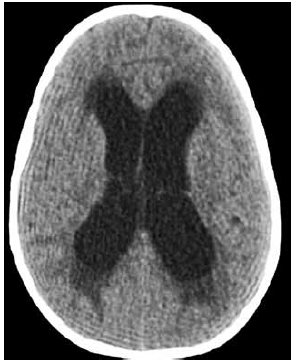

Criança de 2 anos e 8 meses, internada em uma enfermaria, no pós-operatório de uma neurocirurgia, com queixa de sonolência, tem história de tumor de tronco ressecado há 1 semana, sem a realização de derivação ventrículo peritoneal, pois o neurocirurgião achou desnecessário e optou por observar clinicamente a evolução da criança. Nas últimas 6 horas, está mais sonolenta. Foi avaliada pelo médico hospitalista, que solicitou uma tomografia de crânio, e encaminhada pelo técnico de transporte e transferência para UTI após o exame. No exame de entrada na UTI pediátrica: regular estado geral, descorada+, acianótica, anictérica, bradipneica, afebril, letárgica (sem abertura ocular ao chamado ou à dor, gemência aos estímulos dolorosos, resposta motora com retirada inespecífica à dor), FR – 16 irregular Sat – 92% em nebulização com oxigênio 5l/minuto, PA – 155 x 100 mmHg, FC – 65 bpm, pulsos firmes, tempo de enchimento capilar – 2 segundos.

Imagem da tomografia de crânio:

Com relação à conduta inicial, hipótese diagnóstica e conduta a ser tomada imediatamente, assinale a alternativa correta.